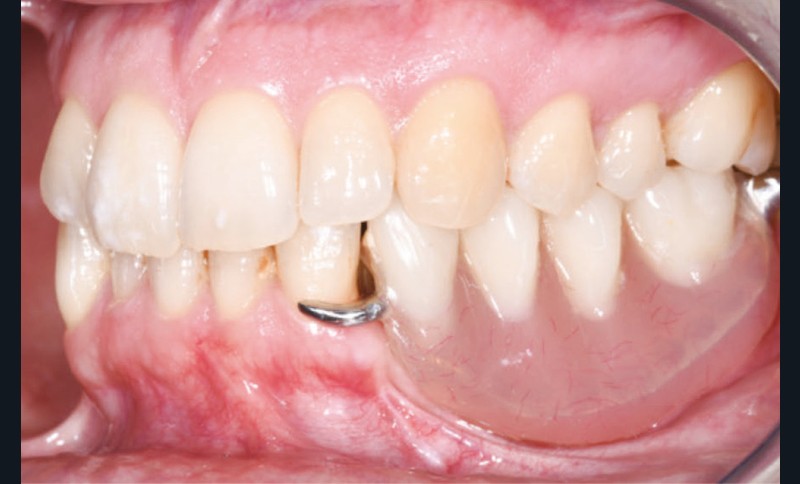

L’examen facial est sans particularités notables. L’examen buccal retrouve un édentement de 33 à 36, compensé par une prothèse amovible, avec une atrophie osseuse transversale et verticale majeure entraînant une augmentation de l’espace prothétique. Il persiste un fin bandeau de gencive kératinisée crestal. Le reste de la denture est sain, l’articulé est en classe I avec un inversé d’articulé sur 13 (fig. 1).